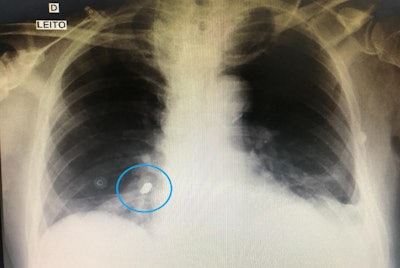

After the tube was placed, the patient underwent a chest x-ray to ensure the tube was in the proper location. However, imaging also revealed a foreign body shaped like a dental prosthetic crown in his right lower lobe bronchus.